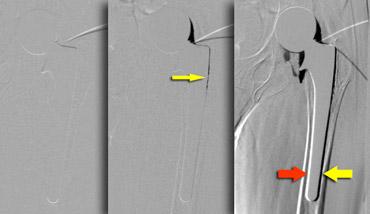

Arthrography

Chụp khớp và nhiễm trùng

Chụp khớp đóng vai trò trong việc đánh giá khả năng nhiễm trùng.

Giá trị của nó trong việc đánh giá khả năng lỏng khớp và đau khớp háng còn hạn chế.

Chụp khớp được sử dụng để xác nhận vị trí trong khớp của kim và dịch được hút ra để cấy vi khuẩn hiếu khí và kỵ khí.

Độ nhạy để phát hiện nhiễm trùng là 66-90%.

Subtraction arthrography reveals contrast leakage in Gruen zone 1 (yellow arrow).Movement of the patient simulates leakage in zone 2 and 3 (red arrow indicates white stripe on medial side which is as broad as black stripe on lateral side ( yellow arrow).

Chụp khớp cản quang và tình trạng lỏng khớp

Việc không có sự lan rộng bất thường của chất cản quang không loại trừ tình trạng lỏng khớp, vì xơ hóa và các tế bào có thể lấp đầy các khoang giao tiếp, ngăn cản sự di chuyển của chất cản quang.

Trong thay khớp háng toàn phần không xi măng, chụp khớp cản quang không chính xác trong việc phát hiện tình trạng lỏng khớp, vì các kênh nhỏ giữa các vùng xương mọc vào có thể tồn tại, cho phép chất cản quang đi qua ngay cả ở những khớp háng nhân tạo còn vững.

Trong thay khớp háng toàn phần có xi măng, sự lan rộng của chất cản quang tại giao diện xương-xi măng có thể là dấu hiệu cho thấy khớp nhân tạo bị lỏng.

Sự thông thương với túi thanh dịch mấu chuyển, vốn thường gặp, càng làm giảm độ nhạy do không thể tạo được áp lực nội khớp tốt (hình).